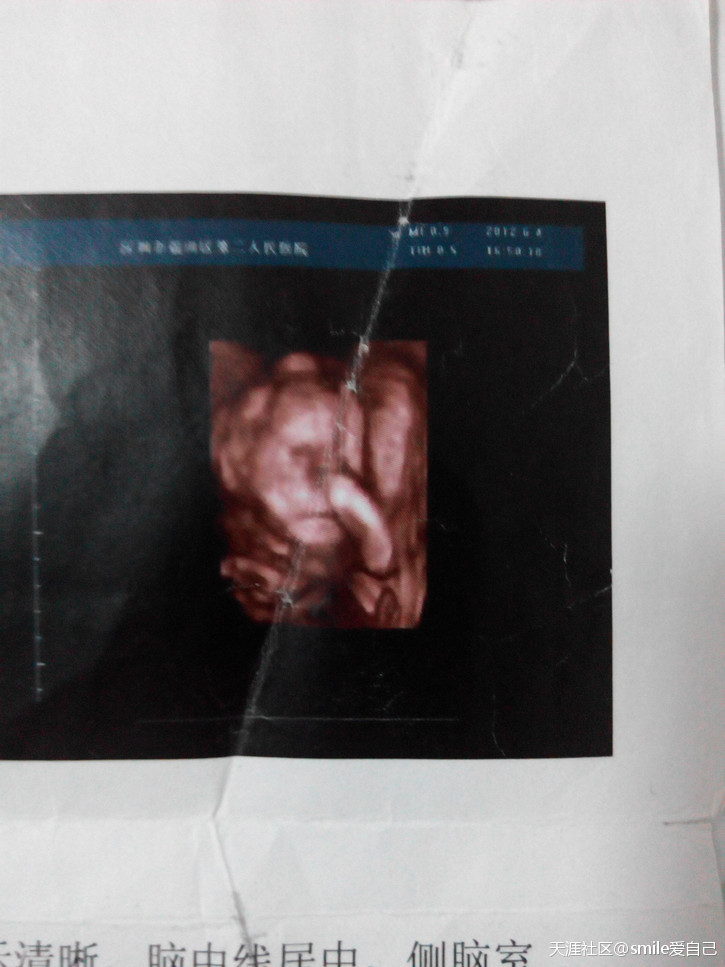

2012年4月检查单,3个多月。

初具人形。

3维彩超。一直没看明白是什么。

记得照回来,曼曼爸爸指着头像说:这是鼻子吗,怎么这么长……

当时去医院照彩超时,曼曼一直用手挡着脸。2只手举成小拳头一起挡在脸前面。给我拍照的2个医生,用手帮我推肚子也推不开曼曼挡住脸的小手,后来两医生都笑坏了,然后叫我去爬楼梯。动一动。

当时在那医院上上下下楼梯,爬楼梯爬了快个把小时,回去照,还是不行。又让我爬楼梯,后来爬得腿软,回去照。

还是不行。

后面医生都要下班了,照个b 超彩超从下午2点开始等,一直搞了一下午也没拍成。

后来医生无奈的说,算了。

第二天再来吧。